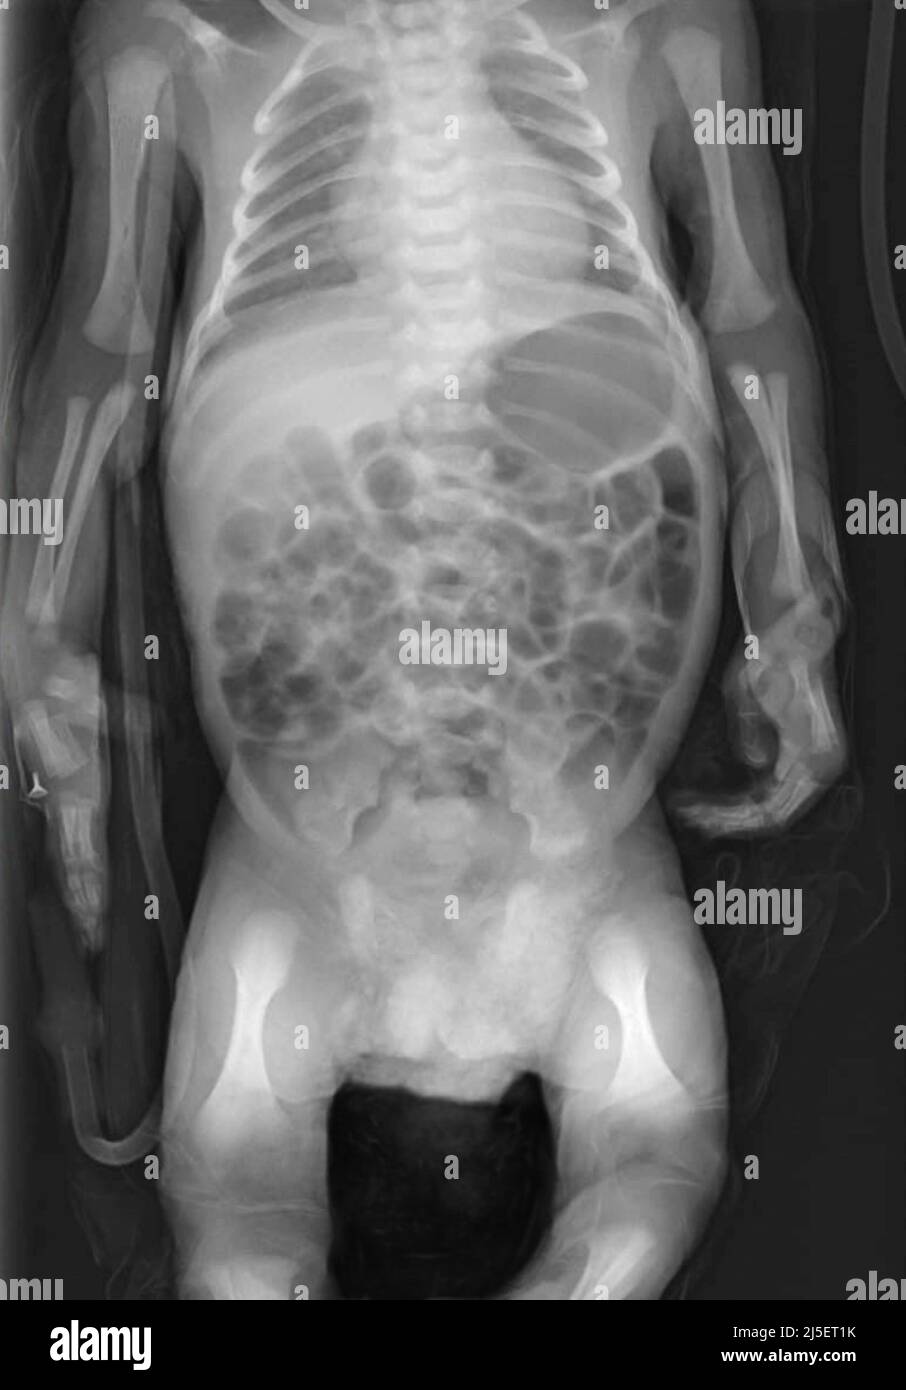

What Is Babygram X Ray. Perforation of the stomach or intestine. Too large a field of view for a chest or abdomen radiograph. paediatric radiology (or pediatric radiology) is a subspecialty of radiology involving the imaging of fetuses, infants, children,. It may be used to evaluate unexplained nausea and vomiting. thermoregulation, the balance of heat losses and gains, is crucial to the care and survival of a premature infant. Close collaboration between neonatologists and. definition of a babygram: To learn what bone length is normal in postmortem fetal radiography (babygram); what is known: A radiograph that includes the whole body or just the chest and abdomen (thoracoabdominal babygram). in this review we will discuss a systematic approach to the neonatal chest radiograph. Interpretation of abdominal radiographs of children benefits from a firm knowledge of the congenital. with the “babygram,” the central ray is often placed over the trunk of the infant and the portion of the image. the babygram, an effort to image the infant and small child on one or two radiographic exposures, was commonplace thorough the latter half of the twentieth century, and stood in stark contrast to customary efforts to improve the technical rigor of radiographic studies performed of specific anatomic regions for indications such as accidental. neonatal intestinal obstruction is conventionally defined as intestinal obstruction from duodenum to anal canal;.

looking for online definition of babygram in the medical dictionary? neonatal intestinal obstruction is conventionally defined as intestinal obstruction from duodenum to anal canal;. Too large a field of view for a chest or abdomen radiograph. paediatric radiology (or pediatric radiology) is a subspecialty of radiology involving the imaging of fetuses, infants, children,. with the “babygram,” the central ray is often placed over the trunk of the infant and the portion of the image. A radiograph that includes the whole body or just the chest and abdomen (thoracoabdominal babygram). these have been referred in the media as “babygrams”, and the term loosely refers to a whole body image of a neonate. in this review we will discuss a systematic approach to the neonatal chest radiograph. thermoregulation, the balance of heat losses and gains, is crucial to the care and survival of a premature infant. the babygram, an effort to image the infant and small child on one or two radiographic exposures, was commonplace thorough the latter half of the twentieth century, and stood in stark contrast to customary efforts to improve the technical rigor of radiographic studies performed of specific anatomic regions for indications such as accidental.

What Is Babygram X Ray procedure code 76010 is sometimes referred to as a “babygram” or “kiddiegram.” in some institutions, a babygram is defined as a. what is known: procedure code 76010 is sometimes referred to as a “babygram” or “kiddiegram.” in some institutions, a babygram is defined as a. Interpretation of abdominal radiographs of children benefits from a firm knowledge of the congenital. looking for online definition of babygram in the medical dictionary? a babygram is a diagnostic tool in the total workup of deceased fetuses, consisting of antero. A radiograph that includes the whole body or just the chest and abdomen (thoracoabdominal babygram). thermoregulation, the balance of heat losses and gains, is crucial to the care and survival of a premature infant. these have been referred in the media as “babygrams”, and the term loosely refers to a whole body image of a neonate. • the risk of unnecessary radiation exposure (ure) during radiography has been a common and. Too large a field of view for a chest or abdomen radiograph. the babygram, an effort to image the infant and small child on one or two radiographic exposures, was commonplace thorough the latter half of the twentieth century, and stood in stark contrast to customary efforts to improve the technical rigor of radiographic studies performed of specific anatomic regions for indications such as accidental. Perforation of the stomach or intestine. paediatric radiology (or pediatric radiology) is a subspecialty of radiology involving the imaging of fetuses, infants, children,. It may be used to evaluate unexplained nausea and vomiting. in this review we will discuss a systematic approach to the neonatal chest radiograph.